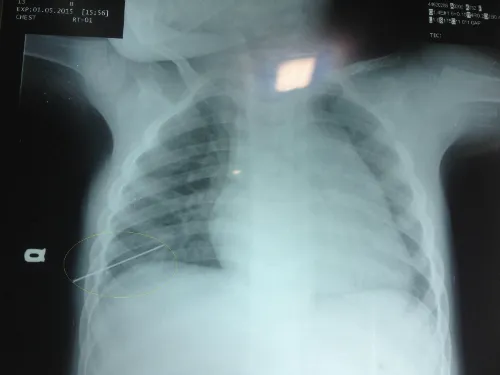

Chiều 1/5, bé trai 3 tuổi ở xã Hoàn Trạch (Bố Trạch, Quảng Bình) được người nhà đưa vào cấp cứu tại Bệnh viện hữu nghị Việt Nam - Cu Ba Đồng Hới. Kết quả X-quang cho thấy một dị vật sắc nhọn đâm xuyên vào lồng ngực bên phải của bé gây thủng phổi.

Hình ảnh phim Xquang của bé trai 3 tuổi cho thấy chiếc kim xuyên lồng ngực phảilàm thủng một lá phổi của bé. Ảnh:Long Nhật.